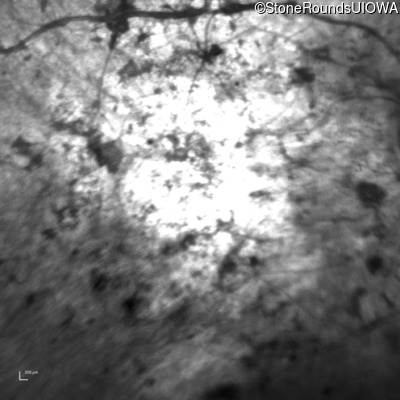

Infrared Fundus Photograph - Right - Hand Motion

Exemplar

Infrared Fundus Photograph - Left - Hand Motion